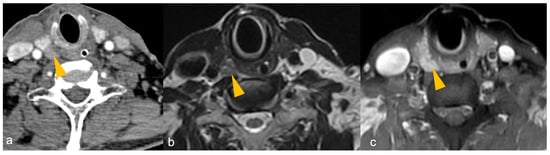

Imaging cannot differentiate parathyroid adenoma (PA) from carcinoma unless cervical adenopathy or distant metastasis is present to suggest parathyroid carcinoma (Figure 5).

Figure 5.

A 32-year-old male with a family history of parathyroid carcinoma presented with elevated serum calcium and parathyroid hormone. (a) Heterogeneously enhancing mass (arrow) arising posterior to the right lobe of thyroid gland on contrast-enhanced computed tomography (CECT), infiltrating the thyroid lobe and occupying the right trachea-oesophageal groove, findings suggestive of parathyroid carcinoma. (b) Osteolytic lesions in bilateral clavicles (arrows) on CECT, suggestive of biopsy-proven brown tumours.

Figure 6 shows CT and MRI of a PA in a patient with PHPT.

Figure 6.

(a–c): CT and MRI of parathyroid adenoma in a patient with primary hyperparathyroidism. (a) Late venous phase 4DCT shows a well defined oval-shaped hypodense lesion (arrowhead) measuring 0.9 × 0.8 cm posterior to the inferior pole of right lobe of thyroid gland, suggestive of parathyroid adenoma. T2WI (b) shows intermediate signal intensity of the parathyroid adenoma, which shows intense post-contrast enhancement (arrowhead in (c)).